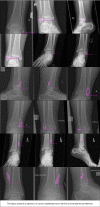

Purpose: Convolutional neural networks (CNNs) are increasingly being developed for automated fracture detection in orthopaedic trauma surgery. Studies to date, however, are limited to providing classification based on the entire image-and only produce heatmaps for approximate fracture localization instead of delineating exact fracture morphology. Therefore, we aimed to answer (1) what is the performance of a CNN that detects, classifies, localizes, and segments an ankle fracture, and (2) would this be externally valid?

Methods: The training set included 326 isolated fibula fractures and 423 non-fracture radiographs. The Detectron2 implementation of the Mask R-CNN was trained with labelled and annotated radiographs. The internal validation (or 'test set') and external validation sets consisted of 300 and 334 radiographs, respectively. Consensus agreement between three experienced fellowship-trained trauma surgeons was defined as the ground truth label. Diagnostic accuracy and area under the receiver operator characteristic curve (AUC) were used to assess classification performance. The Intersection over Union (IoU) was used to quantify accuracy of the segmentation predictions by the CNN, where a value of 0.5 is generally considered an adequate segmentation.

Results: The final CNN was able to classify fibula fractures according to four classes (Danis-Weber A, B, C and No Fracture) with AUC values ranging from 0.93 to 0.99. Diagnostic accuracy was 89% on the test set with average sensitivity of 89% and specificity of 96%. External validity was 89-90% accurate on a set of radiographs from a different hospital. Accuracies/AUCs observed were 100/0.99 for the 'No Fracture' class, 92/0.99 for 'Weber B', 88/0.93 for 'Weber C', and 76/0.97 for 'Weber A'. For the fracture bounding box prediction by the CNN, a mean IoU of 0.65 (SD ± 0.16) was observed. The fracture segmentation predictions by the CNN resulted in a mean IoU of 0.47 (SD ± 0.17).

Conclusions: This study presents a look into the 'black box' of CNNs and represents the first automated delineation (segmentation) of fracture lines on (ankle) radiographs. The AUC values presented in this paper indicate good discriminatory capability of the CNN and substantiate further study of CNNs in detecting and classifying ankle fractures.